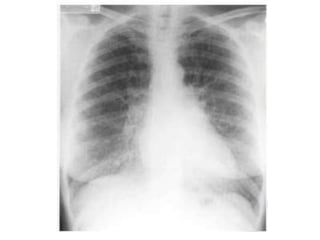

• #69 Mitral stenosis with a normal size heart. In the early years of this chronic disease there is often a normal heart size with only subtle signs of left atrial enlargement being evident. The left atrial appendage is prominent and there is pulmonary venous hypertension.